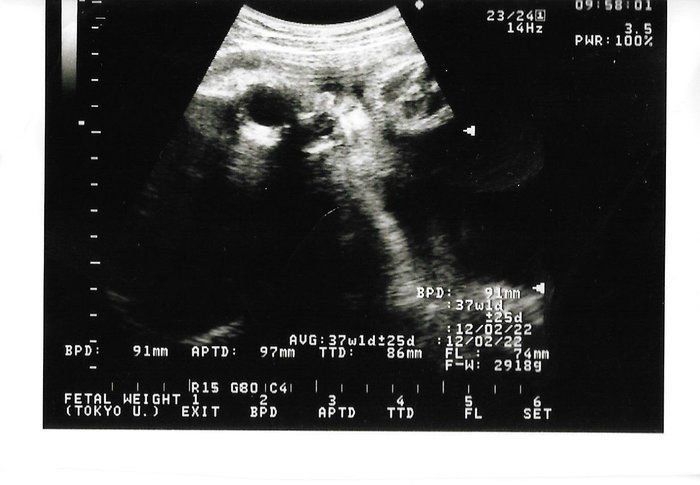

セイコさんの妊娠38週目のエコー写真 頭の大きさは9.4cmのままだけど、体重は3230gに!

最近の主流は「小さく産んで大きく育てる!」だそうで、大体3,000gくらいの赤ちゃんが多いようです。「軽く越えています、もう出てきて大丈夫です」という先生と母の心を知らず、全然おりてくる気配のない娘。大きいと4Dもかわいく写れません。般若のようです!